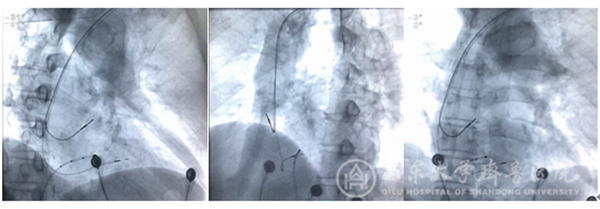

(心室电极固定后位置从左至右分别为RAO 30°、LAO 45°及正位)

(心室电极固定后位置从左至右分别为RAO 30°、LAO 45°及正位)